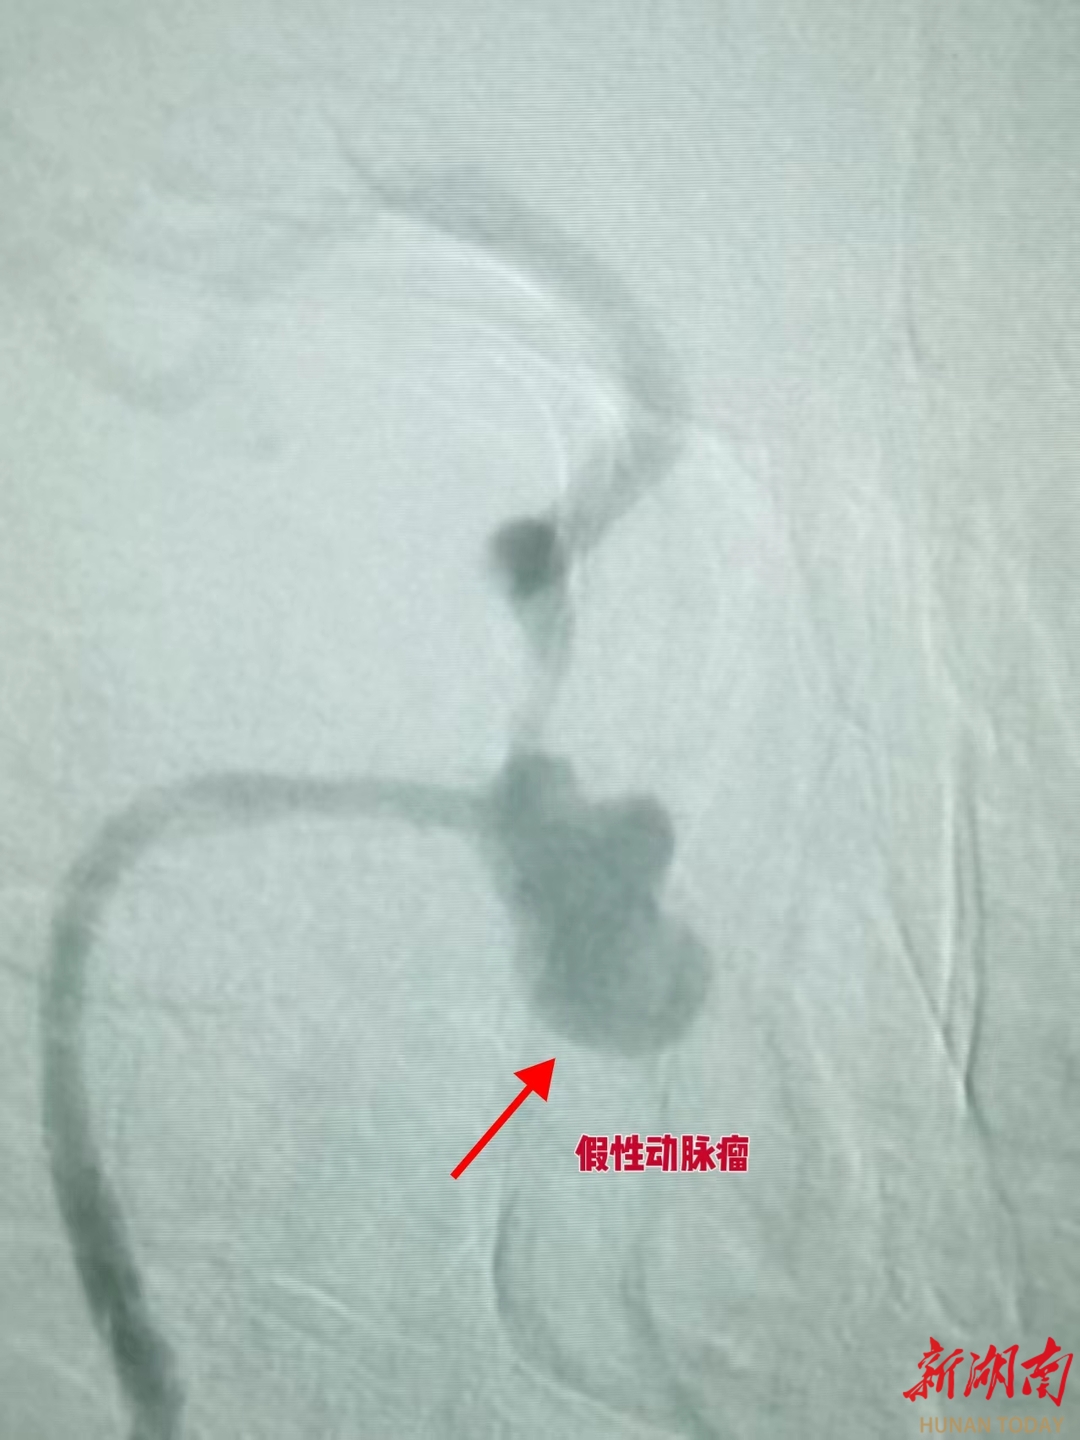

术中造影结果让所有人捏了一把汗,患者右侧颈内动脉 C1-C4 段存在长段重度狭窄,C3 段还形成了巨大假性动脉瘤。更危险的是,动脉高压的持续冲击让瘤体较术前 CTA 检查明显增大膨出,形态愈发不规则,破裂风险已箭在弦上,而患者鼻腔仍在不断涌出鲜红色血液。

介入治疗的极速高效在此刻体现得淋漓尽致。在龙文兴医生的精准操作下,手术材料与栓塞用弹簧圈如同被赋予了生命,通过针眼大小的创口直达病灶,这种精准微创的特点,既避免了大开刀带来的二次创伤,又能让治疗直达核心。短短30多分钟,手术团队忙而不乱,一道道医嘱精准下达,一个个操作一气呵成。当最后一枚弹簧圈到位,复查造影显示假性动脉瘤未再显影,造影剂无外溢,患者鼻腔出血彻底停止,这场生死竞速,以医生的胜利告终。